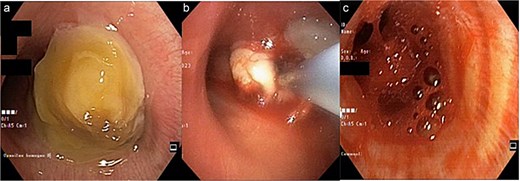

Bronchoscopy results (Fig. 2) showed that an intraluminal mass entirely covered the proximal lumen of the right main bronchus. A cryobiopsy was performed on the mass in the proximal lumen. After a cryobiopsy, bleeding occurred in the right main bronchus. Suctioning was performed, cold saline was administered, and then the bleeding stopped. The bronchoscope was withdrawn, and the procedure was completed. Five minutes after the procedure the patient experienced desaturation. A re-bronchoscopy was performed for re-evaluation and found massive bleeding in the right main bronchus which spread to the left main bronchus (Fig. 2). Suctioning was performed, cold saline and epinephrine were administered. Not long after that, the patient experienced cardiac arrest. CPR was performed, and the patient got the return of spontaneous circulation so he was transferred to the ICU. Three days after treatment in ICU the patient passed away due to acute respiratory failure.

(a) Mass at the proximal of the right main bronchus, left main bronchus was still patent; (b) a cryobiopsy was performed on an intraluminal mass in the right main bronchus; (c) bleeding 5 minutes after the cryobiopsy was done which extended to the left main bronchus so it covered both main bronchus.